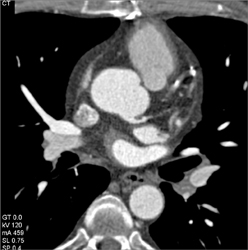

Patent Bypass Grafts But Plaque Distally-see Full Sequence